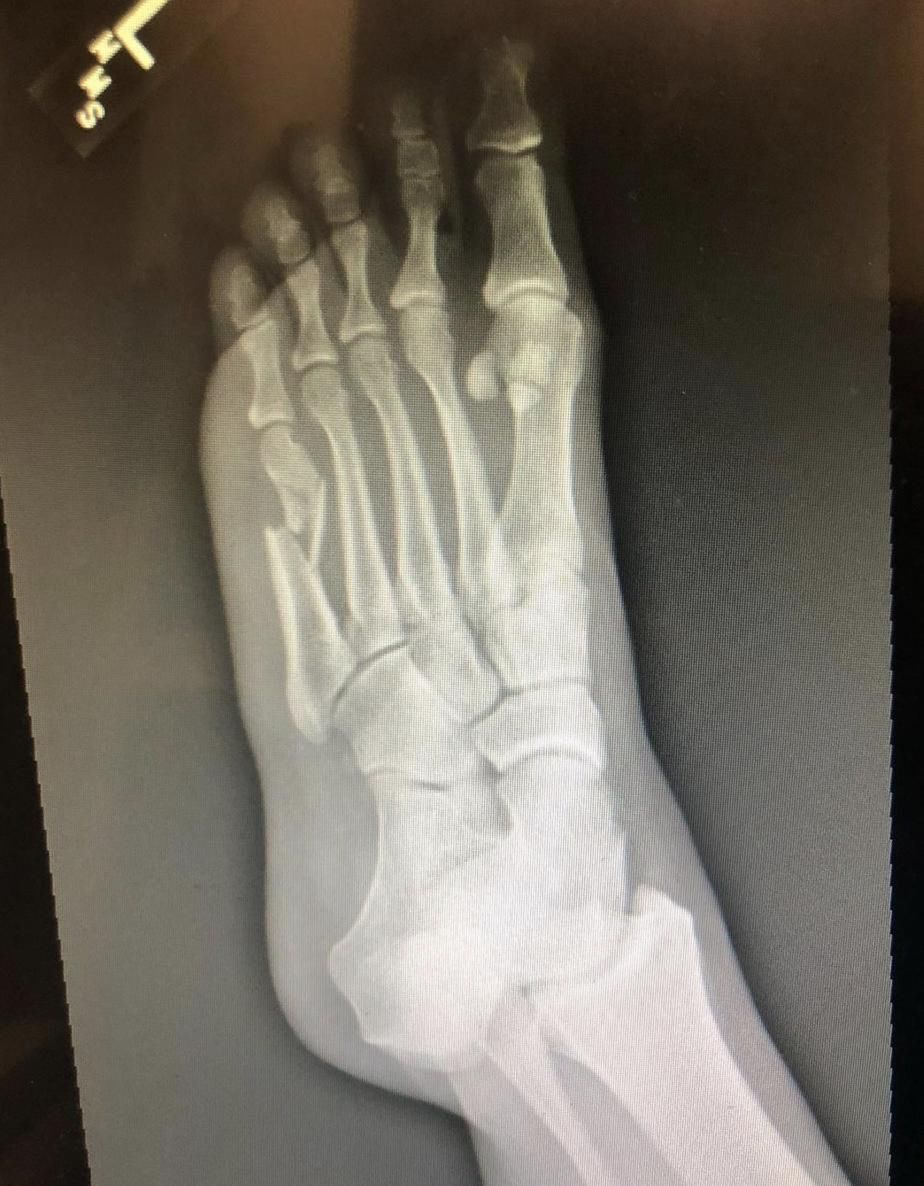

Gwiazda postanowiła cofnąć się do tego momentu i dopiero teraz opublikowała zdjęcie rentgenowskie, na którym widać jej złamaną kość. To nie wygląda za dobrze:

Zdjęcie rentgenowskie mojej złamanej stopy sprzed dwóch lat!!!